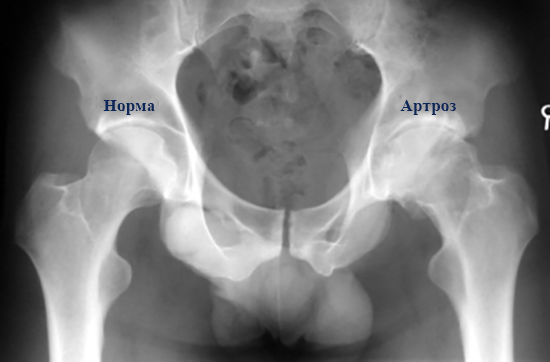

Рентгеновские снимки: Синовит тазобедренного сустава